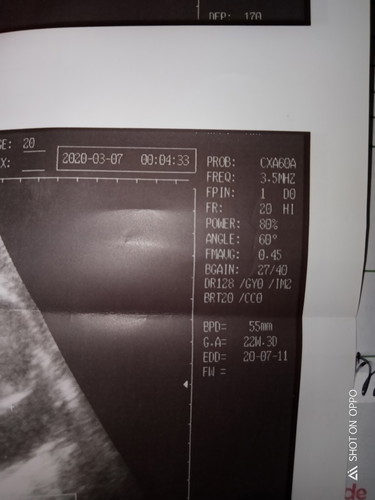

Hi Tanong Lang Po according sa Last menstruation ko Bilang nang Duedate ko is July 29 nagpa ultrasound ako Ayan Po sa Ultrasound may nakalagay na EDD 20-7-11 Medyo naguluhan ako Tas may nakasulat pa na Expect due Aug 6